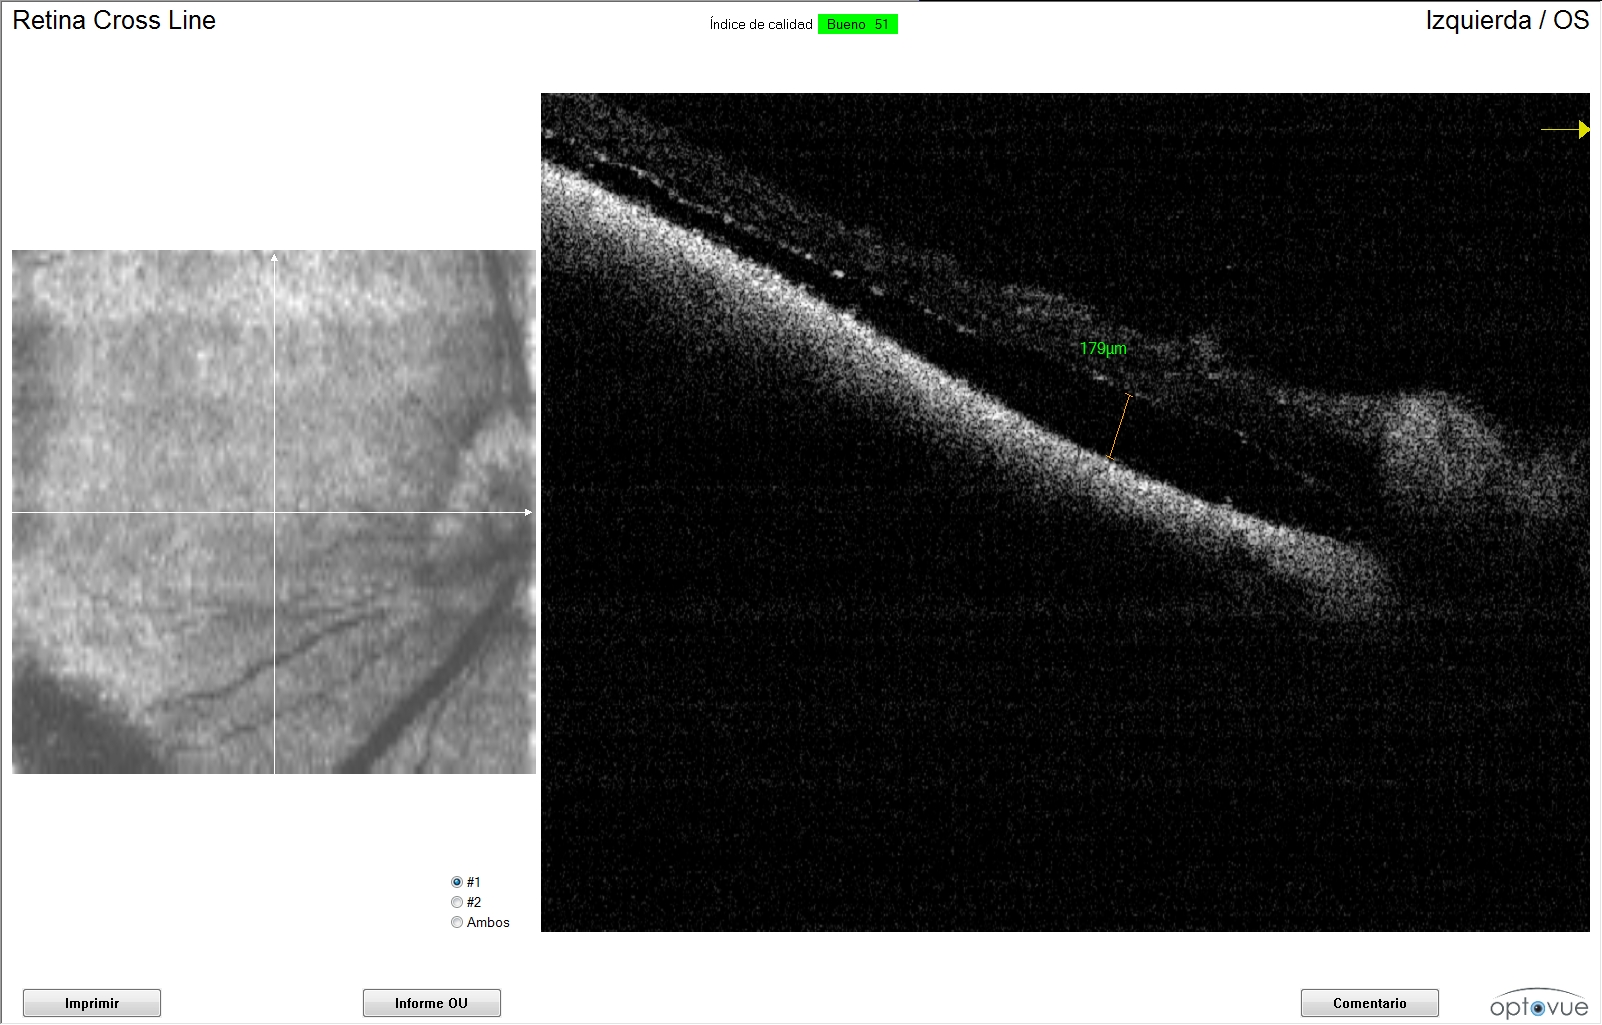

Se utilizó un tomógrafo de coherencia óptica dominio espectral (Optovue®ivue SD-OCT, Freemont, CA) para llevar el seguimiento del caso viendo así su evolución, respuesta al tratamiento y modulación de éste dependiendo de las imágenes obtenidas.El caso estudiado es un Beagle de 4 años de edad que acudió a consulta para una segunda opinión por pérdida de visión.

De cada una de la imágenes de OCT se midió la distancia entre la neuroretina y el epitelio pigmentado de la retina (EPR). Evaluando de esta manera, la evolución y respuesta al tratamiento del desprendimiento de retina exudativo. Se cápturaron imágenes de la zona tapetal, no tapetal y región peripapilar.

Se obtuvieron imágenes de OCT donde progresivamente se ha disminuido la distancia entre la neuroretina y el EPR, apreciando de esta manera una reducción progresiva del exudado inflamatorio.Fueron analizadas todas las capturas de la zona peripapilar.

La primera medición que obtuvimos del ojo derecho mediante la OCT fue de 363 μm. Las siguiente mediciones en cada seguimiento fueron de 235, 80, 67 y 34 μm. Respecto al ojo izquierdo se obtuvo una primera medición de la separación de la neuroretina del EPR de 645 micras. Con valores de 363, 179, 28 y 0 μm en la siguientes revisiones.

La recuperación de la respuesta de amenaza y reflejos pupilares normales fueron a partir de la quinta revisión, llevando en ese momento 42 días de tratamiento, manteniéndose hasta la actualidad con una buena función visual recuperando sus hábitos y costumbres habituales.

Aunque los reflejos se recuperasen, y los propietarios notaban una mejoría notable de la función visual todavía fueron detectadas zonas de exudado retiniano mediante la OCT, por lo que se desaconsejo parar el tratamiento hasta que hubiese desaparecido todo el exudado inflamatorio. Hemos conseguido, de esta manera, llevar un mejor control del problema, obteniendo de una manera objetiva y cuantitativa el grado de mejoría.